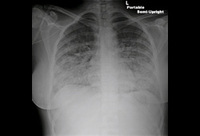

Pericardial tamponade: admission chest x-ray

Usalan C, Atalar E, Vural FK. Pericardial tamponade in a 65-year-old woman. Postgrad Med J. 1999;75:183-184; used with permission.